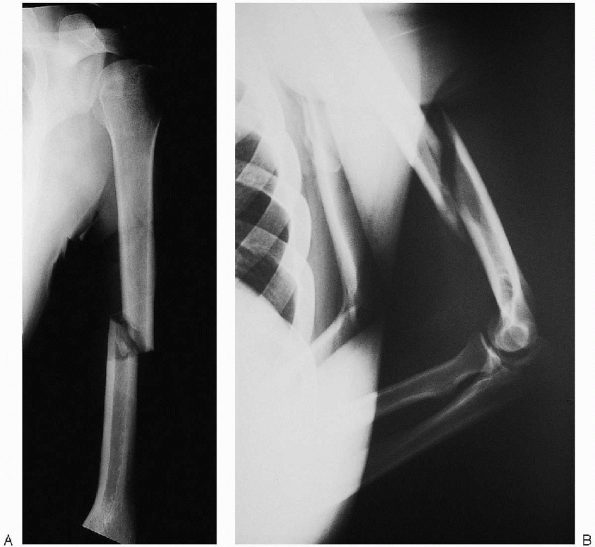

FIGURE 7-3.

FIGURE 7-4. Anteroposterior (A) and lateral (B) radiographs demonstrating a displaced humeral shaft fracture.